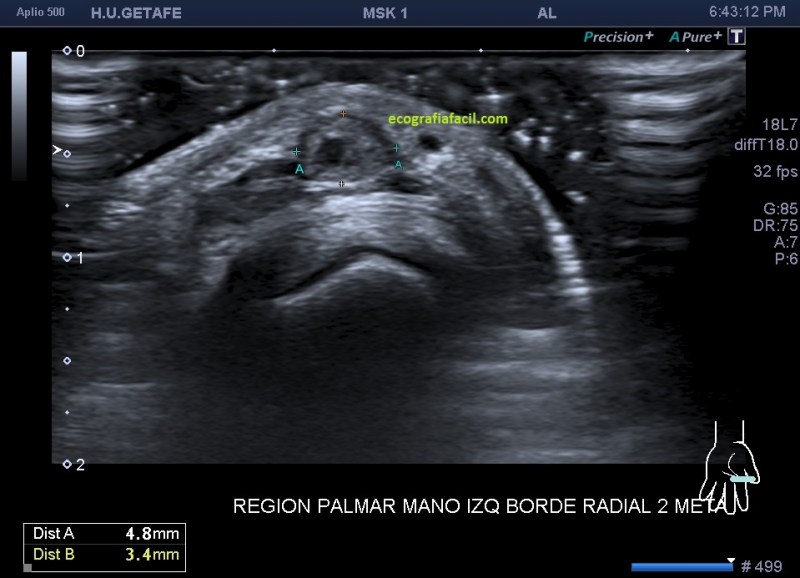

El paciente del caso que te expongo hoy como primer post del 2021 es un paciente de uno 40 años que nota desde hace un año un pequeño bultoma en la palma de la mano, en la región flexora en el eje largo del 2 dedo, a la altura de la articulación metacarpofalángica, ligeramente radial, viene referido del traumatólogo.

En esta primera imagen me encuentro, primero, un estructura heterogénea, redonda, ligeramente ovalada con un centro anecoico y un halo grueso e hipoecogénico.

Lo segundo es delimitarla bien, tener bien estudiada la anatomía de referencia, imagen 2, respecto de la ecoestructura patológica y su propia ecoarquitectura. Por supuesto aplicamos el protocolo de referencia, localización, estudio, medición y vascularización que hoy ves resumido en estas 5 imágenes ya que el estudio lo enfoqué en el estudio de algo vascular.

El corte en eje largo como te indica el pictograma es muy importante, en teoría debería haber encontrado una estructura redondeada en eje corto y tubular en eje largo, como debiera corresponder a esta lesión vascular, pero los hallazgos no arrojaron dicha imagen.

Demostré el pulso en ambos ejes, pero no pude comprobar la estructura tubular en longitudinal…el motivo, el tamaño de la estructura y su gruesa pared que puedes apreciar en ambos ejes y que correspondía a una incremento de la pared del propio vaso, vaso que se encontraba parcialmente trombosado por este crecimiento de su pared, habitual en estas lesiones post traumáticas, donde el propio vaso sangra y esa sangre se colecciona alrededor el mismo.